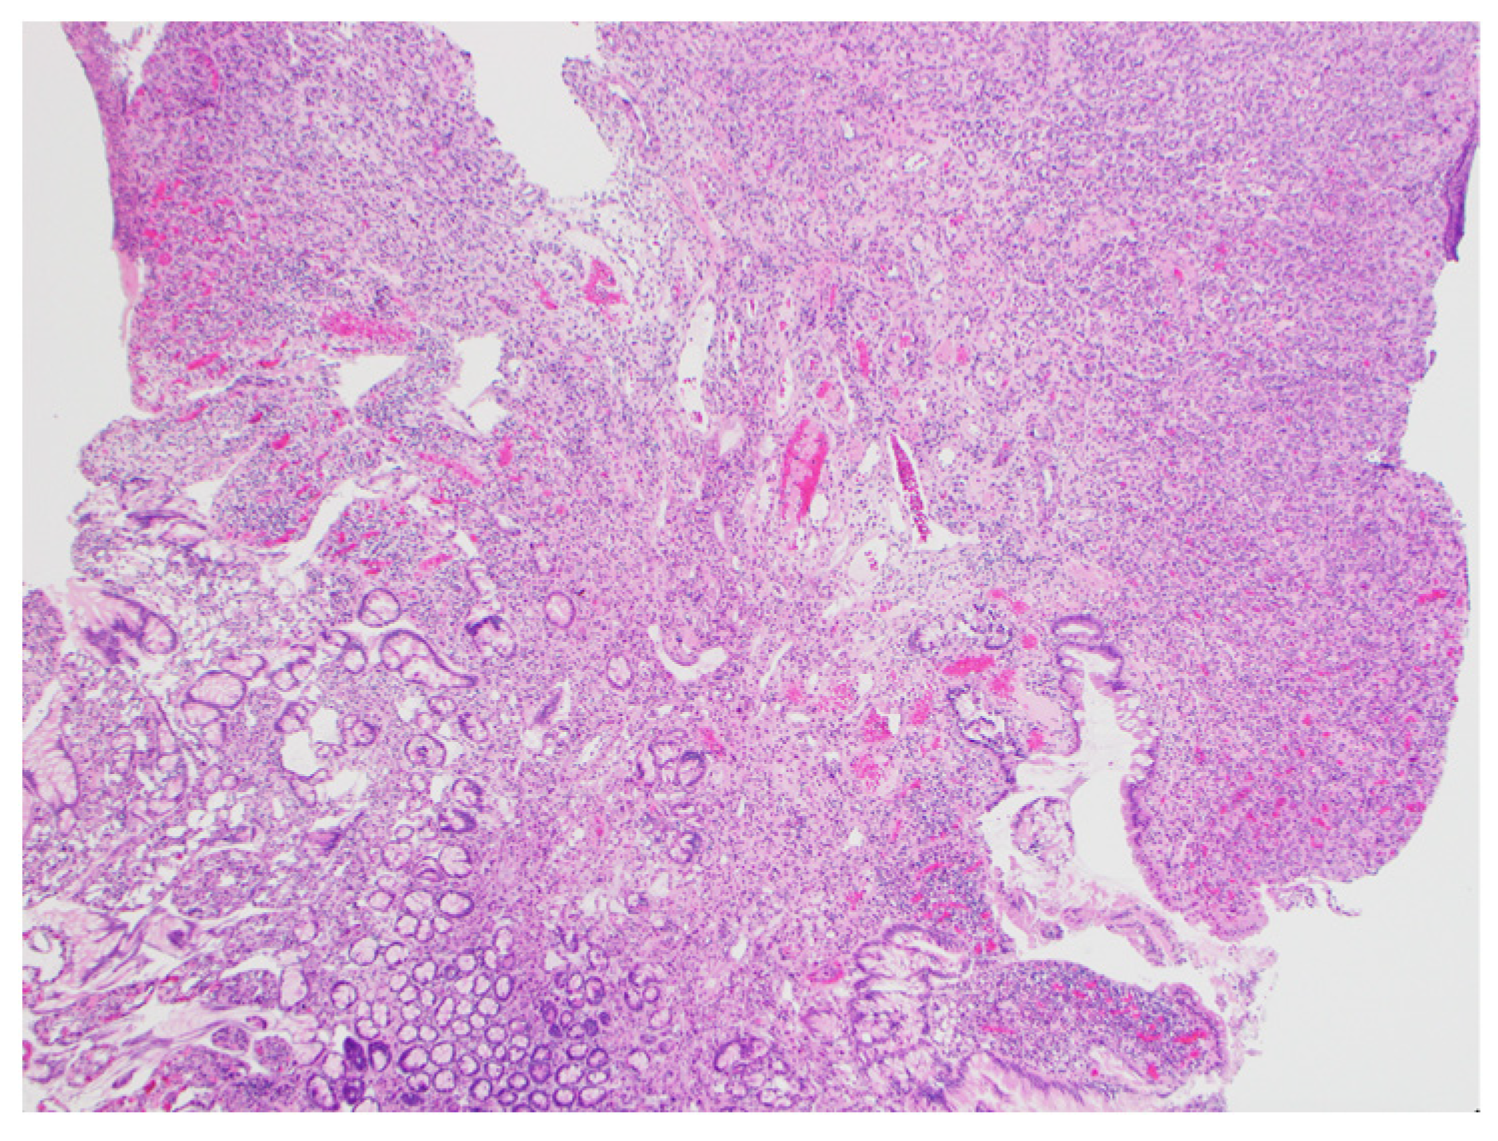

According to these findings, we suspected a non-epithelial tumor such as a hemangioma. Endoscopic mucosal resection (EMR; Snare Master®, Olympus, Tokyo, Japan) was attempted, but manipulating the endoscope was difficult, so the lesion was snared and resected before energization. Clips (EZ clip®, Olympus, Tokyo, Japan) were used to prevent further bleeding and the position of the lesion was marked with a tattoo. Histological examination of the lesion revealed the dense growth of capillaries; the lesion was therefore diagnosed as a capillary hemangioma (Figure 3). Our follow-up of the patient was uneventful for 11 months and revealed that he had recovered from anemia.

Figure 3. Histological examination of the lesion that was identified as a small intestinal capillary hemangioma with a positive vertical margin (hematoxylin–eosin).